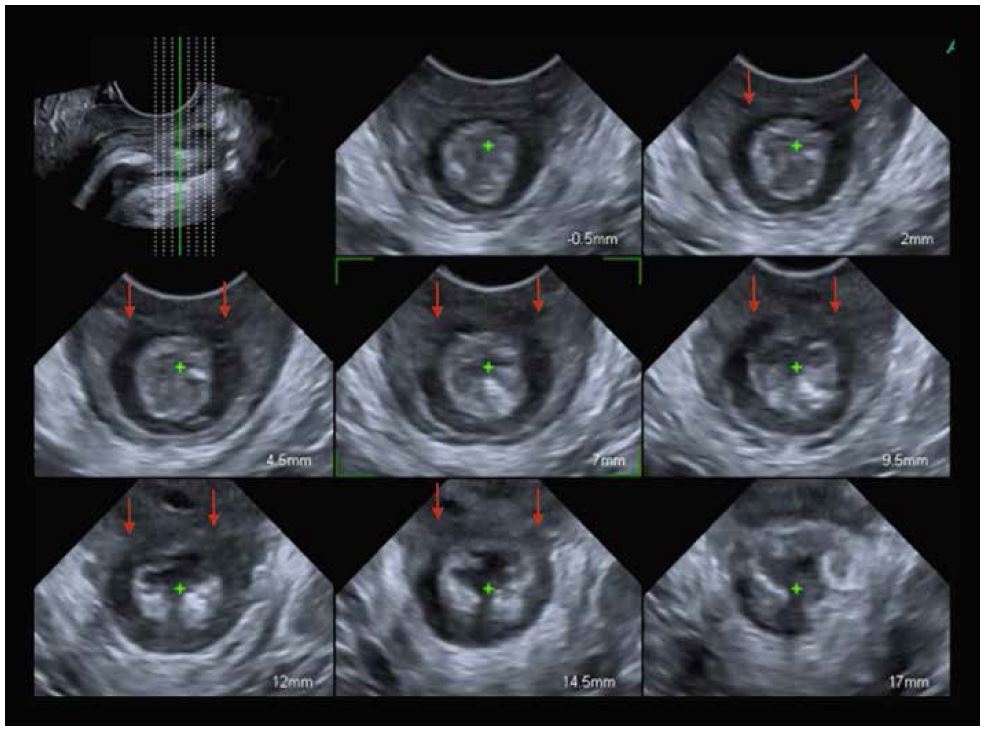

Анальний сфінктер

Для оцінки анального сфінктера датчик слід розташувати поперечно над промежиною, нахиливши зонд до анального отвору (мал. 13). Бажано фіксувати об’єм під час скорочення, щоб краще розрізняти тканини. Мультипланарна оцінка дозволяє проаналізувати весь анально-сфінктерному комплекс, розташувавши першу площину на пуборектальному м’язі, а останню – на анальному краю (всього 8 площин) (мал. 14). Відстань між площинами залежить від довжини анального каналу і дозволяє дослідити безперервність сфінктерного комплексу (червона стрілка на мал. 15), а також його товщину, переривчастість, локалізацію дефекту та зміни слизової оболонки анального отвору.

Малюнок 13. Додавання додаткового схематичного малюнка розміщення датчика. LAM: м'яз-підіймача відхідника, IN: внутрішній сфінктер, E: зовнішній сфінктер, M: слизова оболонка прямої кишки

Малюнок 14. Багатоплощинне дослідження для аналізу анально-сфінктерного комплексу.

Малюнок 15. Пошкодження внутрішнього і зовнішнього анального сфінктера на 12 годині (червона стрілка).